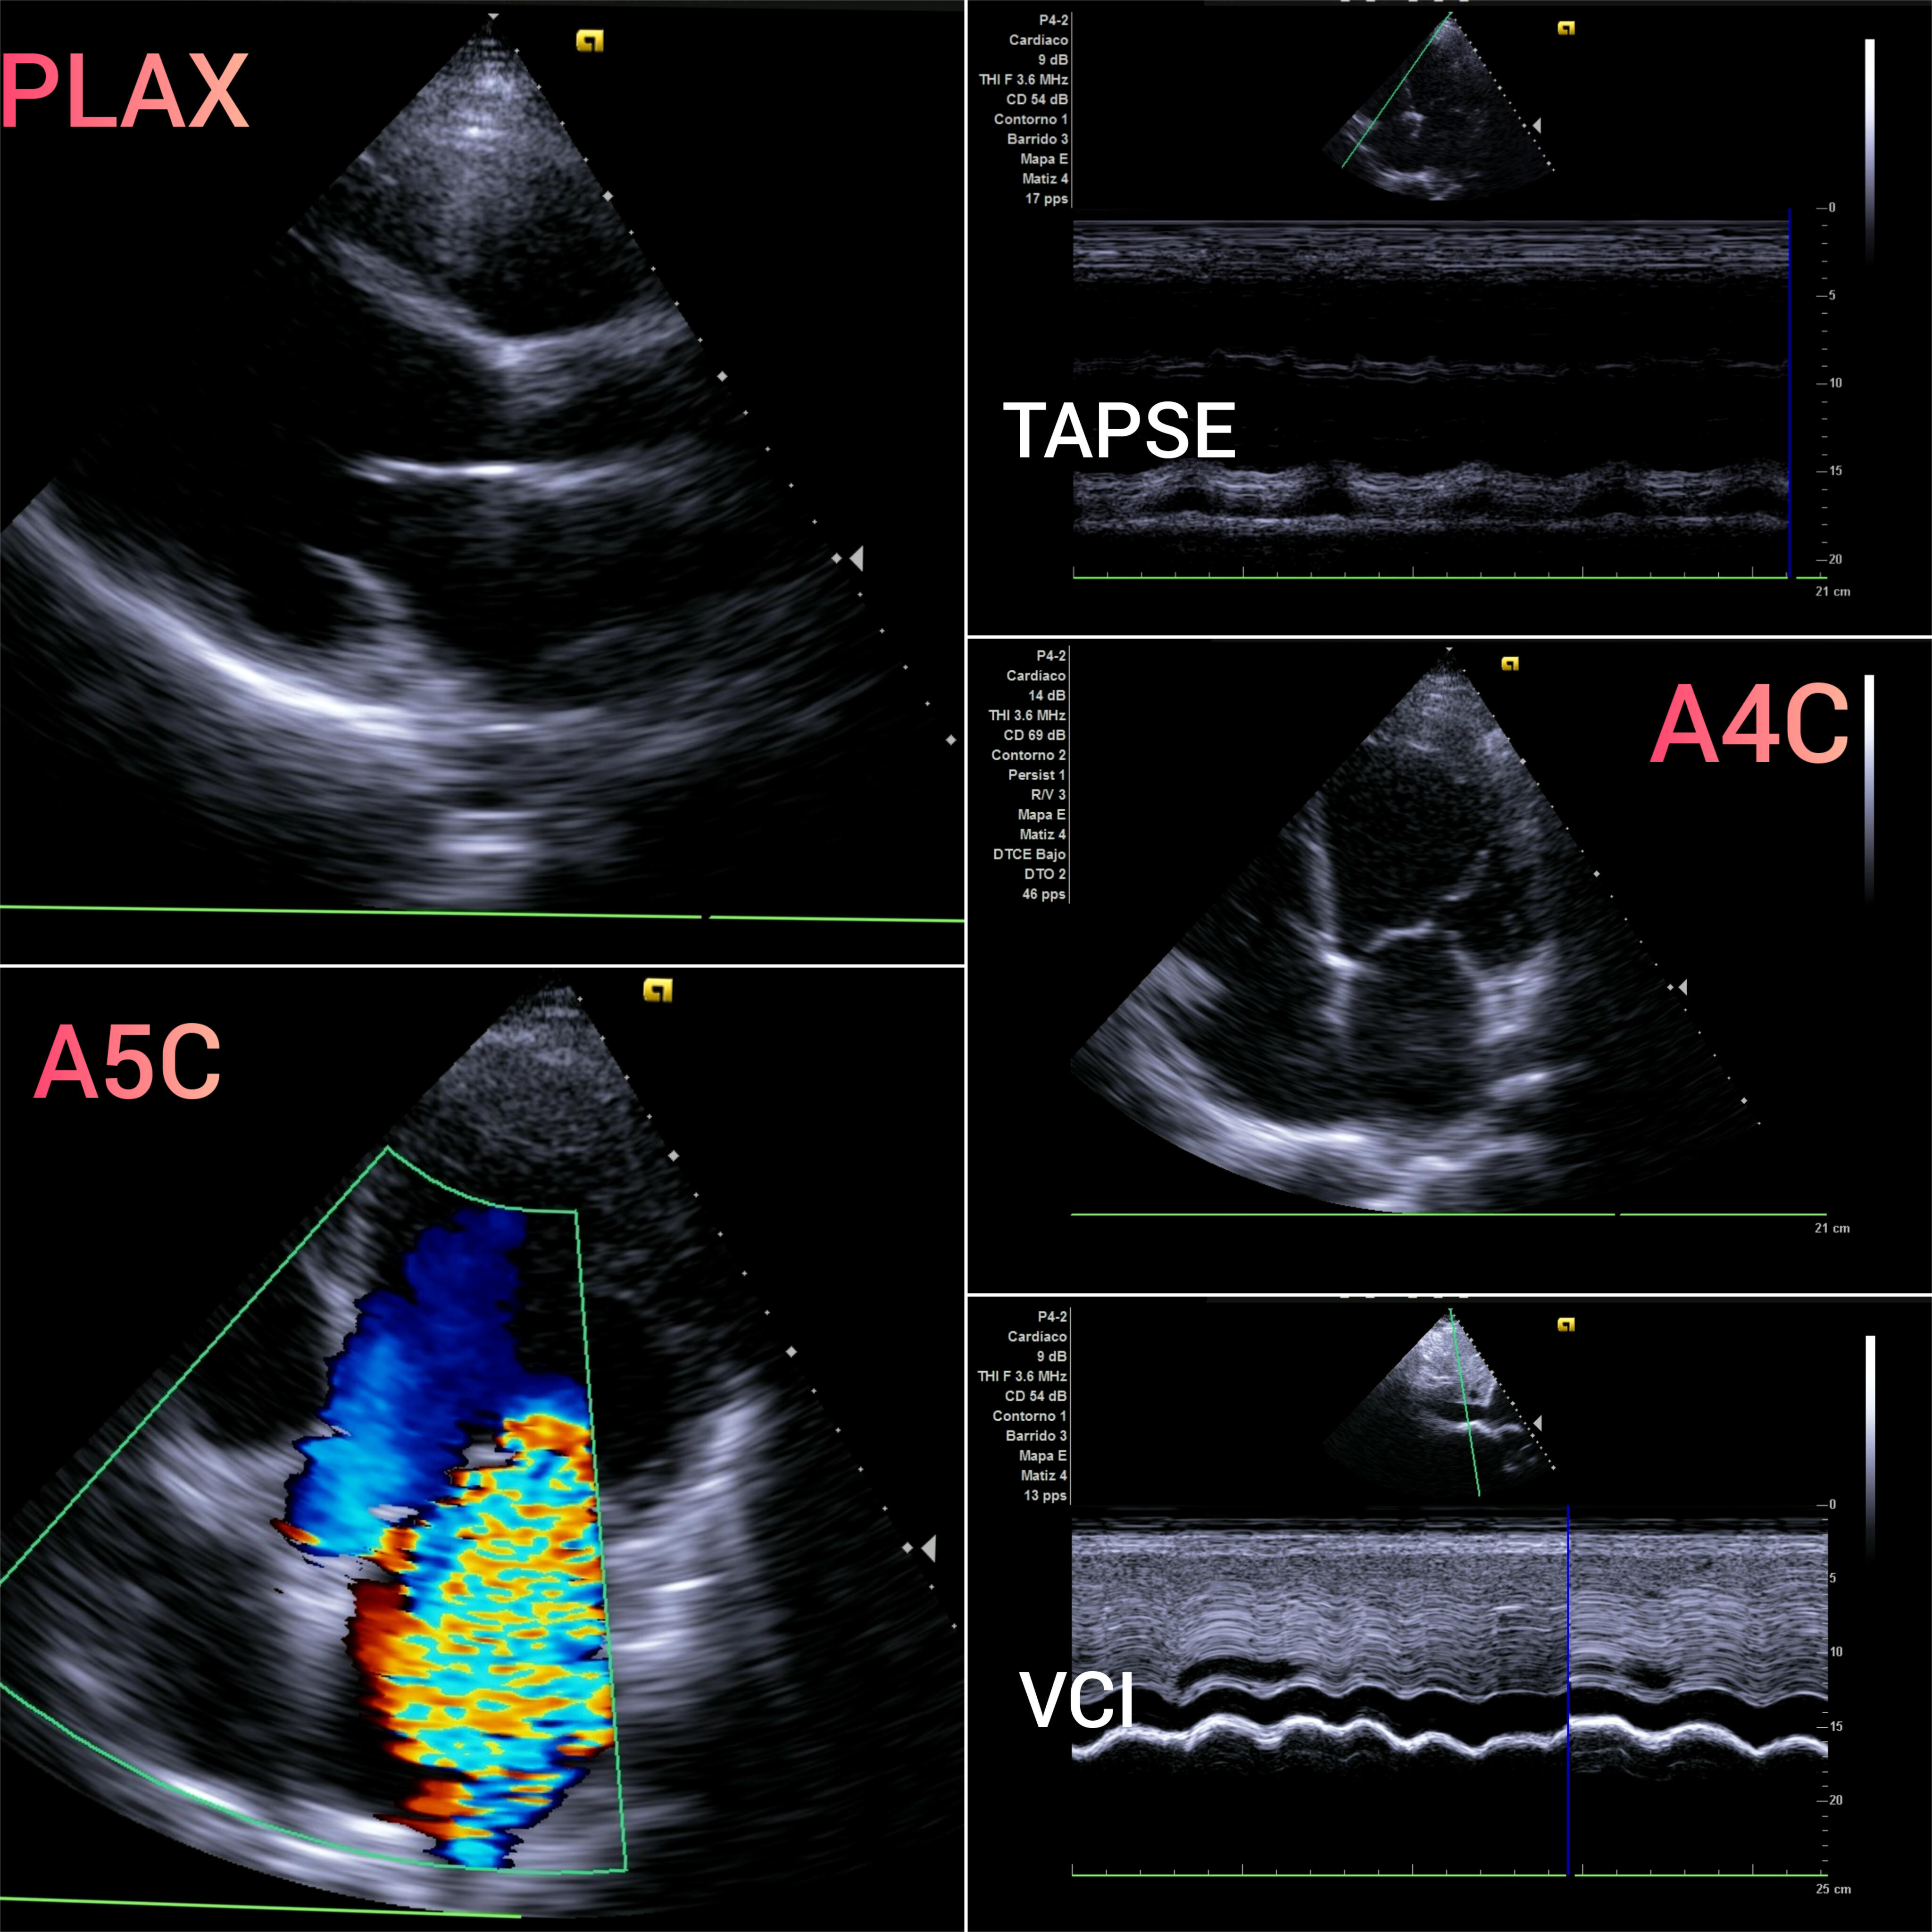

A las técnicas ya presentes en consulta como la ecografía abdominal a nivel de vena cava inferior (VCI) y ecografía pulmonar, se incorpora la ecocardioscopia y el protocolo VEXUS.

La ecocardioscopia fuera del ámbito de la cardiología ya ha demostrado utilidad en escenarios clínicos como disnea, soplo o alteraciones electrocardiográficas.

La sobrecarga de presión o volumen en un paciente provoca congestión intersticial, Nefrología aplica el protocolo VEXUS «Venous EXcess UltraSounds» tanto en el diagnóstico como en el seguimiento de múltiples patologías. Se han descrito 4 perfiles de congestión.

La ecografía complementa otras pruebas complementarias clásicas como: ECG, Rx Tórax y analítica (hierro, TSH, ProBNP y CEA125). Ya incorporadas, la ecografía abdominal para la VCI, la ecografía pulmonar y la ecocardioscopia, es el momento del protocolo VEXUS en el diagnóstico y seguimiemto de patologías como: Insuficiencia Cardíaca, s. CardioRenal o s. Nefrótico.